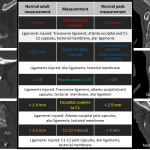

- Offset of the lateral masses of C1 with respect to the occipital condyles consistent with atlanto-occipital subluxation

- Bilateral atlanto-occipital subluxation (extensive ligamentous injury subsequently confirmed on MRI)

Offset of the lateral masses of C1 with respect to the occipital condyles concerning for ligamentous injury. Recommend MRI for further evaluation.